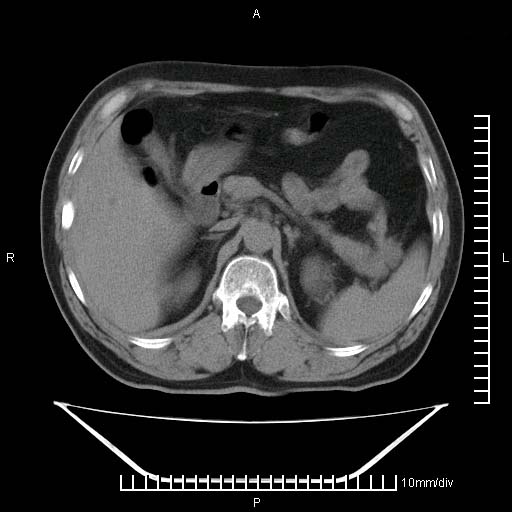

标题: CT25082:肝脏增强:男性,70岁 [打印本页]

标题: CT25082:肝脏增强:男性,70岁

患者以心脏疾病收住院,腹部无明显症状,b超查肝脏有占位。

牛眼征,中心坏死无强化,外缘强化,最外缘又见低密度,考虑转移,与脓肿鉴别

肝内多发转移瘤,右下肺炎症并少量胸水。胃壁增厚建议胃镜,胰尾部“病变”为肠管。

1)肝脏多发性转移瘤(不排除胰尾癌转移所致可能)。2)腹水。3)右侧少量胸腔积液。

右下胸膜肥厚。

胰尾占位?结肠脾曲?

ct25082 结果:转移瘤

外院mr结果:胰尾恶性占位。